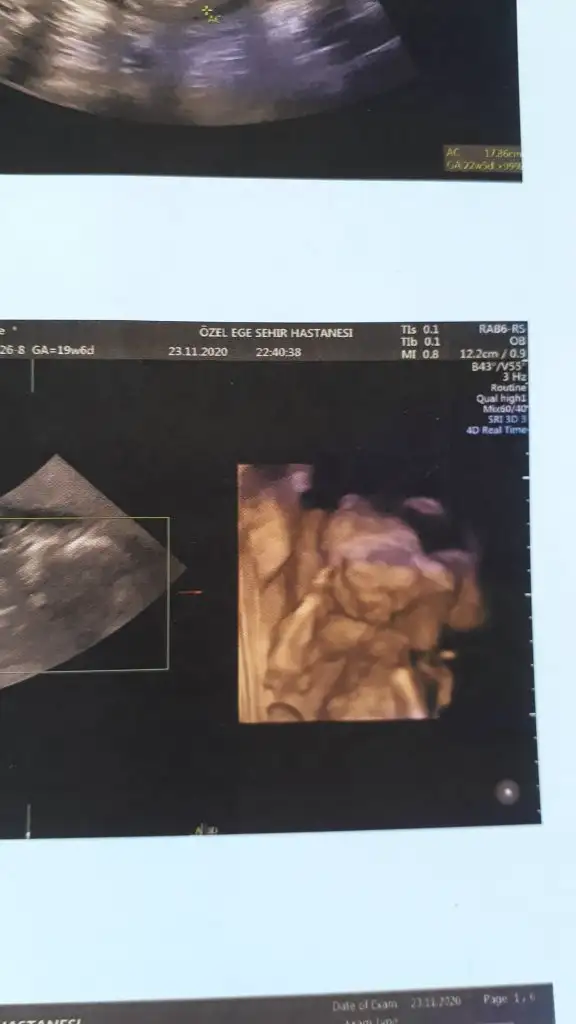

Genelde meyve suyu ya da çikolata diyorlar .. Ayrıntılı güzel geçer inşallah..Kızlar yarın ayrıntılı ultrasonum var. Her kontrole gittiğimizde ya ters duruyor, ya da pozisyonunu hiç değiştirmiyor. Bebeği hareketlendirmek için neler yemek içmek lazım?

Benim gideceğim doktorun sekreteri ultrasona girmeden yarım saat önce tatlı bir şeyler yiyebilirsin dedi. Ama benim kız genelde kahvaltıdan sonra hareketleniyorKızlar yarın ayrıntılı ultrasonum var. Her kontrole gittiğimizde ya ters duruyor, ya da pozisyonunu hiç değiştirmiyor. Bebeği hareketlendirmek için neler yemek içmek lazım?

Benimkinde hep secdedeydi sıfır hareket bu sefer giderken bir muz yedim bir palet çikolata ve filtre kahve yürüyüş ayrıntılıya bir girdik doktor bebeğimi durduramadıKızlar yarın ayrıntılı ultrasonum var. Her kontrole gittiğimizde ya ters duruyor, ya da pozisyonunu hiç değiştirmiyor. Bebeği hareketlendirmek için neler yemek içmek lazım?